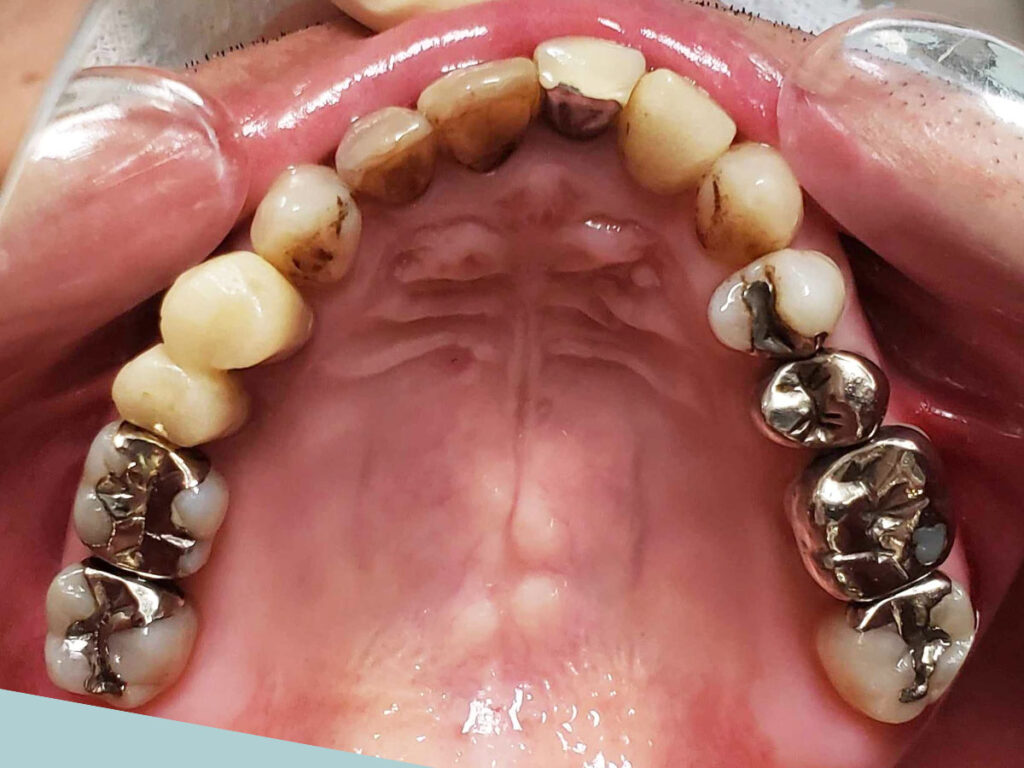

術前

- 初診:2019年、40代男性、非喫煙者、アレルギー体質(花粉症)

- 主訴:左下の銀歯の歯茎が腫れた。他の歯医者から治せないと言われたので、口の中全体を診てほしい。できれば歯並びも治して、歯を白くしたい。

- 矯正診断:3級骨格性の反対咬合

- 治療方針:以前に治療したほぼ全ての歯の再治療(虫歯治療、歯内療法、歯周処置)、矯正用インプラントを用いたワイヤー矯正、修復処置(被せ物)、保定(上マウスピース、下ワイヤー)、メンテナンス